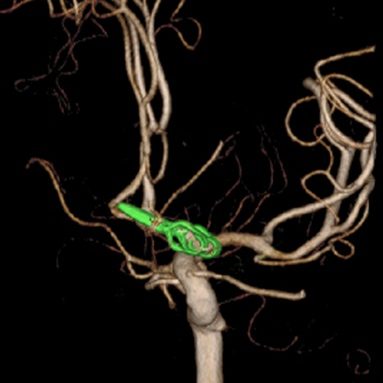

当科で治療した年々大きくなった大型脳底動脈瘤の3次元脳血管撮影像です。脳動脈瘤と周囲の血管の状態が非常によく分かるため、術前に十分な検討が可能でした。

術前

術後、脳底動脈瘤はコイルにより完全に塞栓され、正常の脳底動脈の血流は維持されている。

脳動脈瘤に対するコイル塞栓術

術後 瘤内塞栓にて動脈瘤への血流は認めない